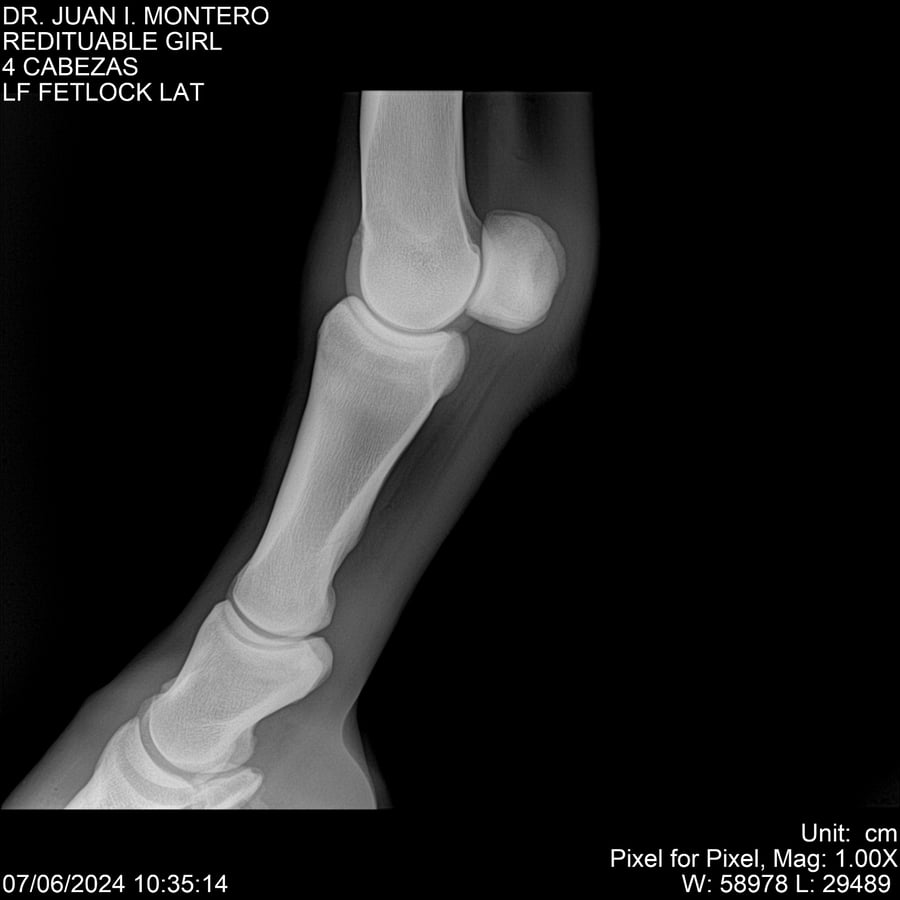

LOTE 19, REDITUABLE GIRL Lote Anterior Volver al remate Lote Siguiente Ficha Contacto Montevideo - Ficha del Lote Identificador: #281096 Categoría: Yeguarizos Montevideo - 79 Visualizaciones ClicData Contacto Empresa: Abelenda N. R., Walter Hugo Nombre*: Teléfono* : E-mail* : Mensaje Enviar Registrese gratis Este contenido Exclusivo está disponible sólo para usuarios registrados Ingresar